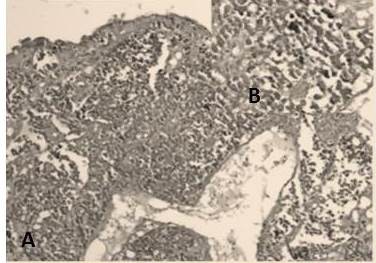

En el estudio los casos de carcinomas neuroendocrinos estuvieron representados en su mayoría por carcinomas neuroendocrinos de células pequeñas con 80 % de los casos (Figura 13), los carcinomas de células grandes (Figura 14) fueron 13,3 % y se observó un caso 6,7 % de tumor carcinoide típico (Figura 14) (Cuadro 10).

Los tumores neuroendocrinos mantuvieron la misma clasificación en tumores carcinoides típicos y atípicos (G1 y G2), carcinomas neuroendocrinos de células pequeñas y carcinomas neuroendocrinos de células grandes (G3) (30) en nuestra revisión obtuvimos 15 (7,4 %) casos de carcinomas neuroendocrinos, el tumor neuroendocrino más frecuente fue el carcinoma neuroendocrino de células pequeñas con 12 casos, se revisaron 2 casos de carcinoma neuroendocrino de células grandes y un tumor carcinoide típico. Estos resultados son similares a los encontrados por Machado A. (3) quien en su estudio concluye que el carcinoma neuroendocrino de células pequeñas es el tercer carcinoma más frecuente.